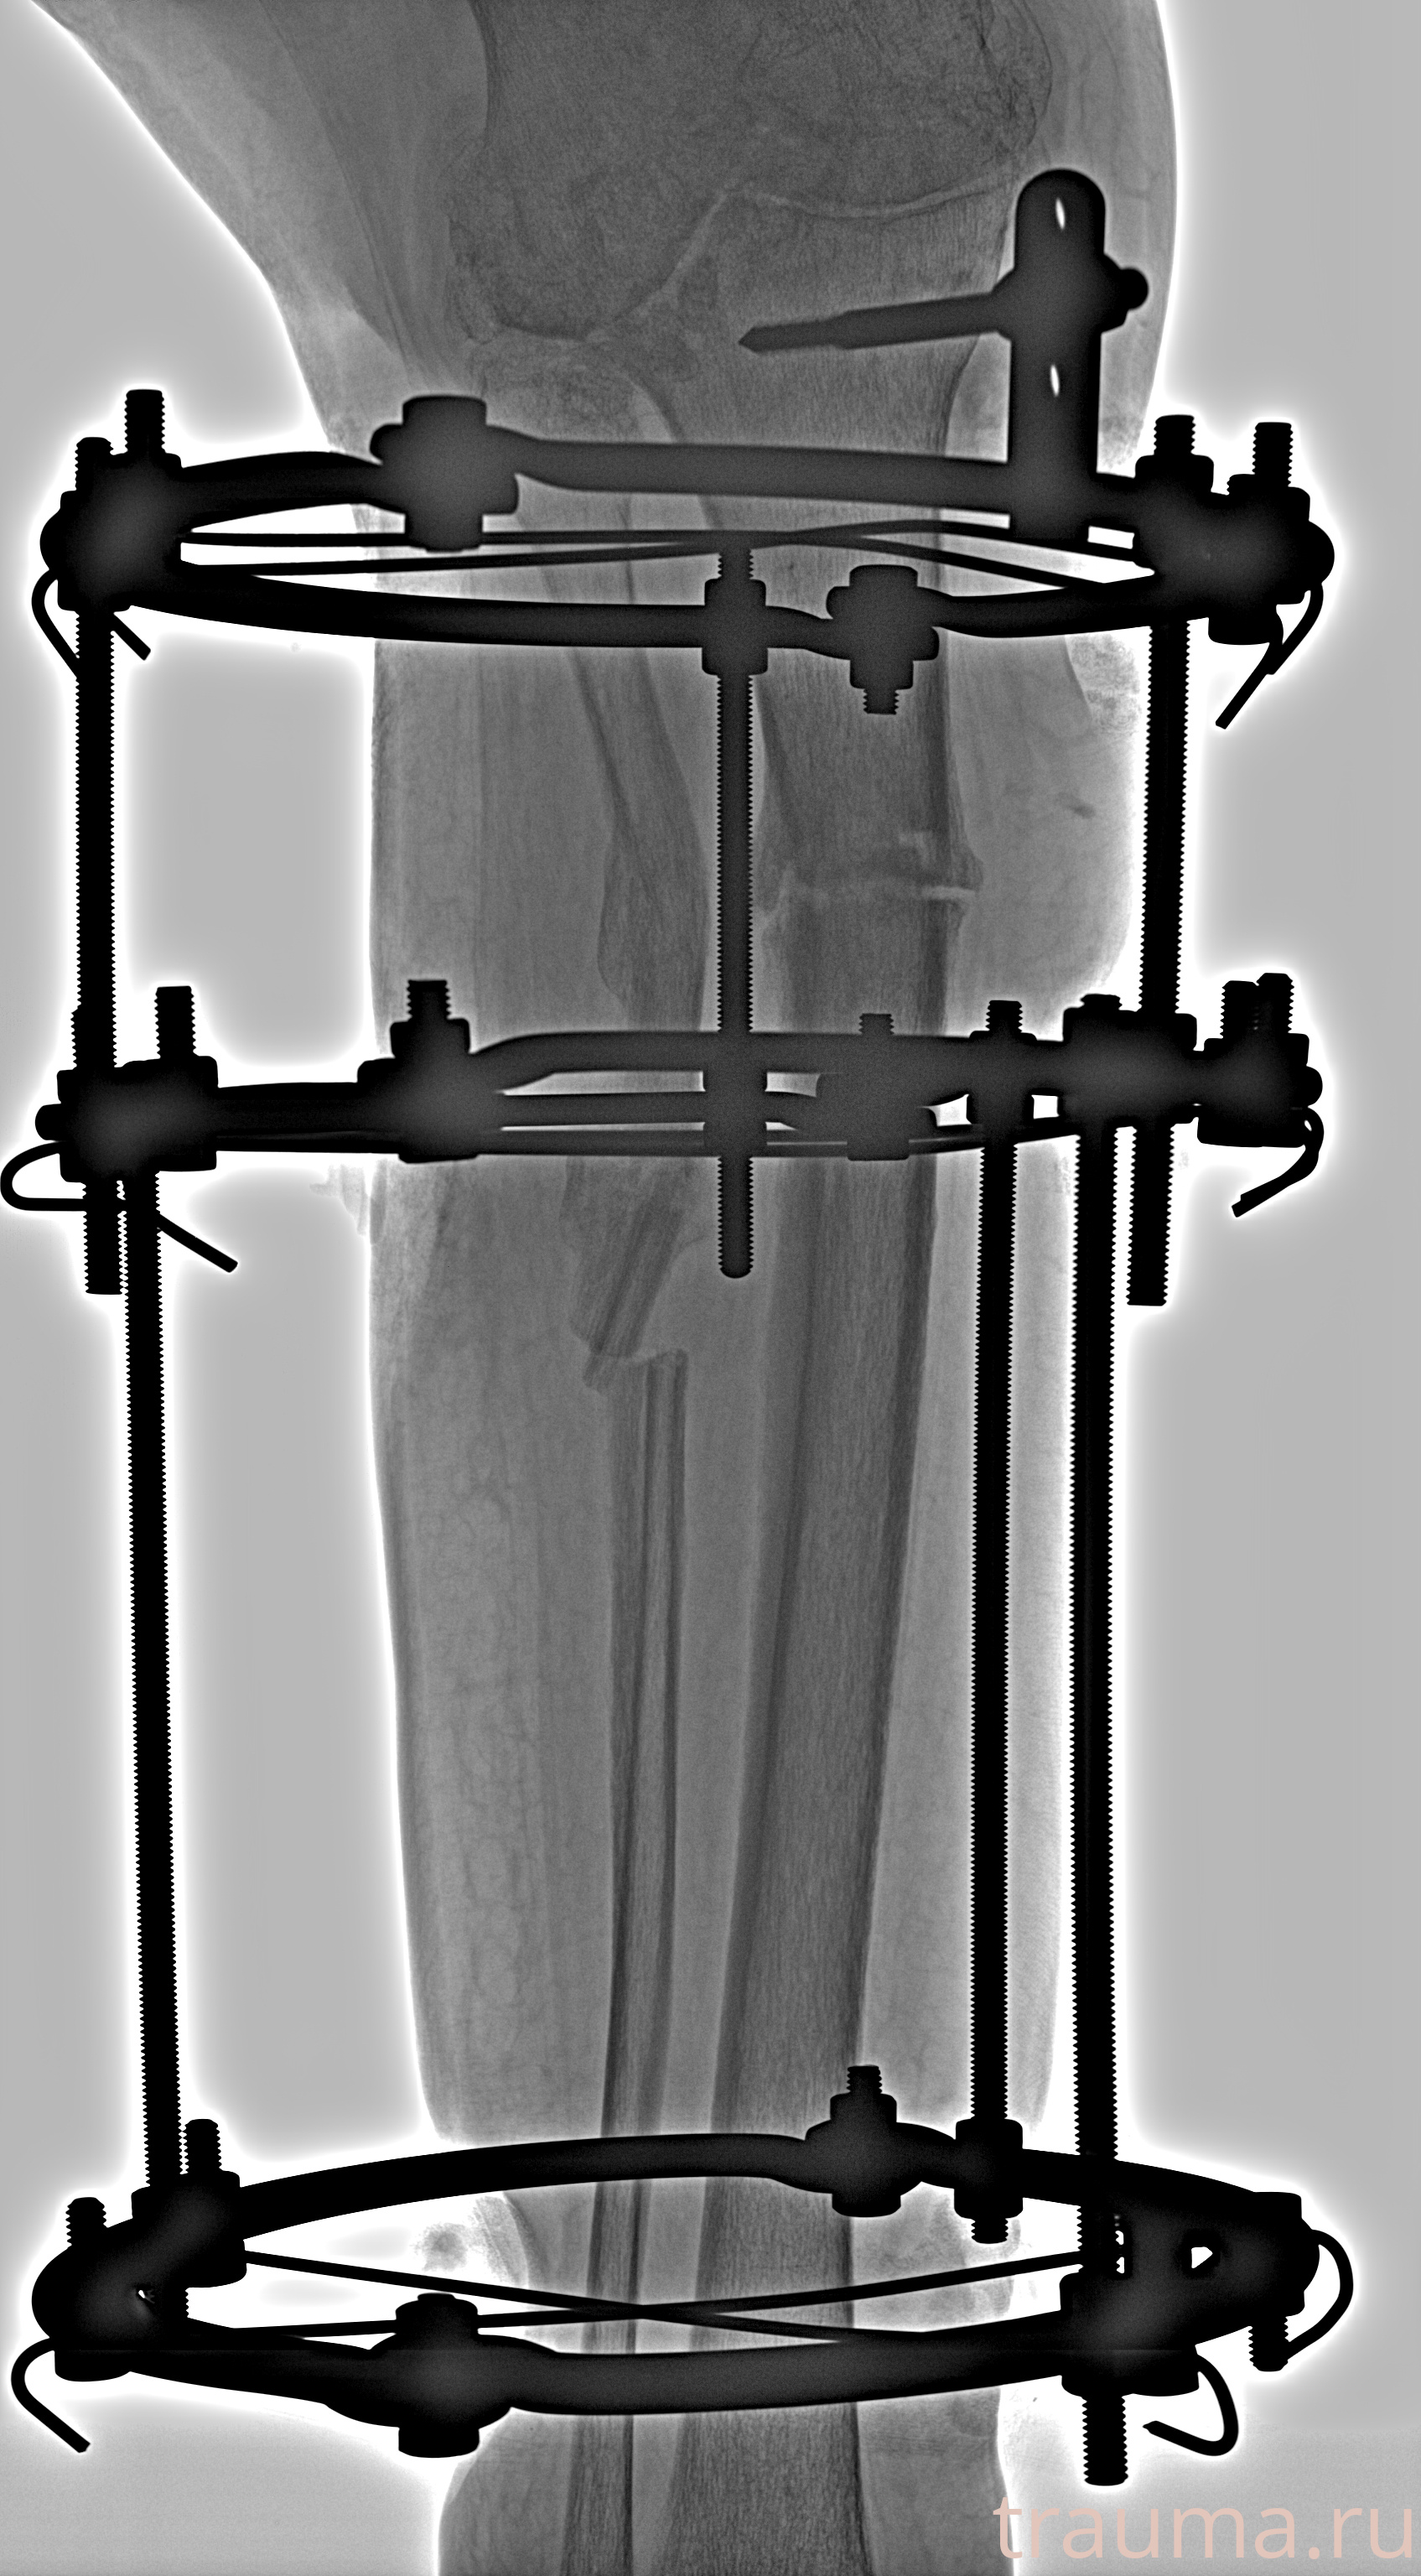

Рентгенограммы

Левая

Рентген на дому: по вашему адресу приезжает врач-рентгенолог, травматолог-ортопед с мобильным рентгеновским аппаратом, проводит диагностику травмы или заболевания, делает необходимые рентгенограммы, дает рекомендации по дальнейшему лечению. Получить качественные снимки в домашних условиях возможно благодаря уникальной методике, разработанной МосРентген Центром для института  Склифосовского